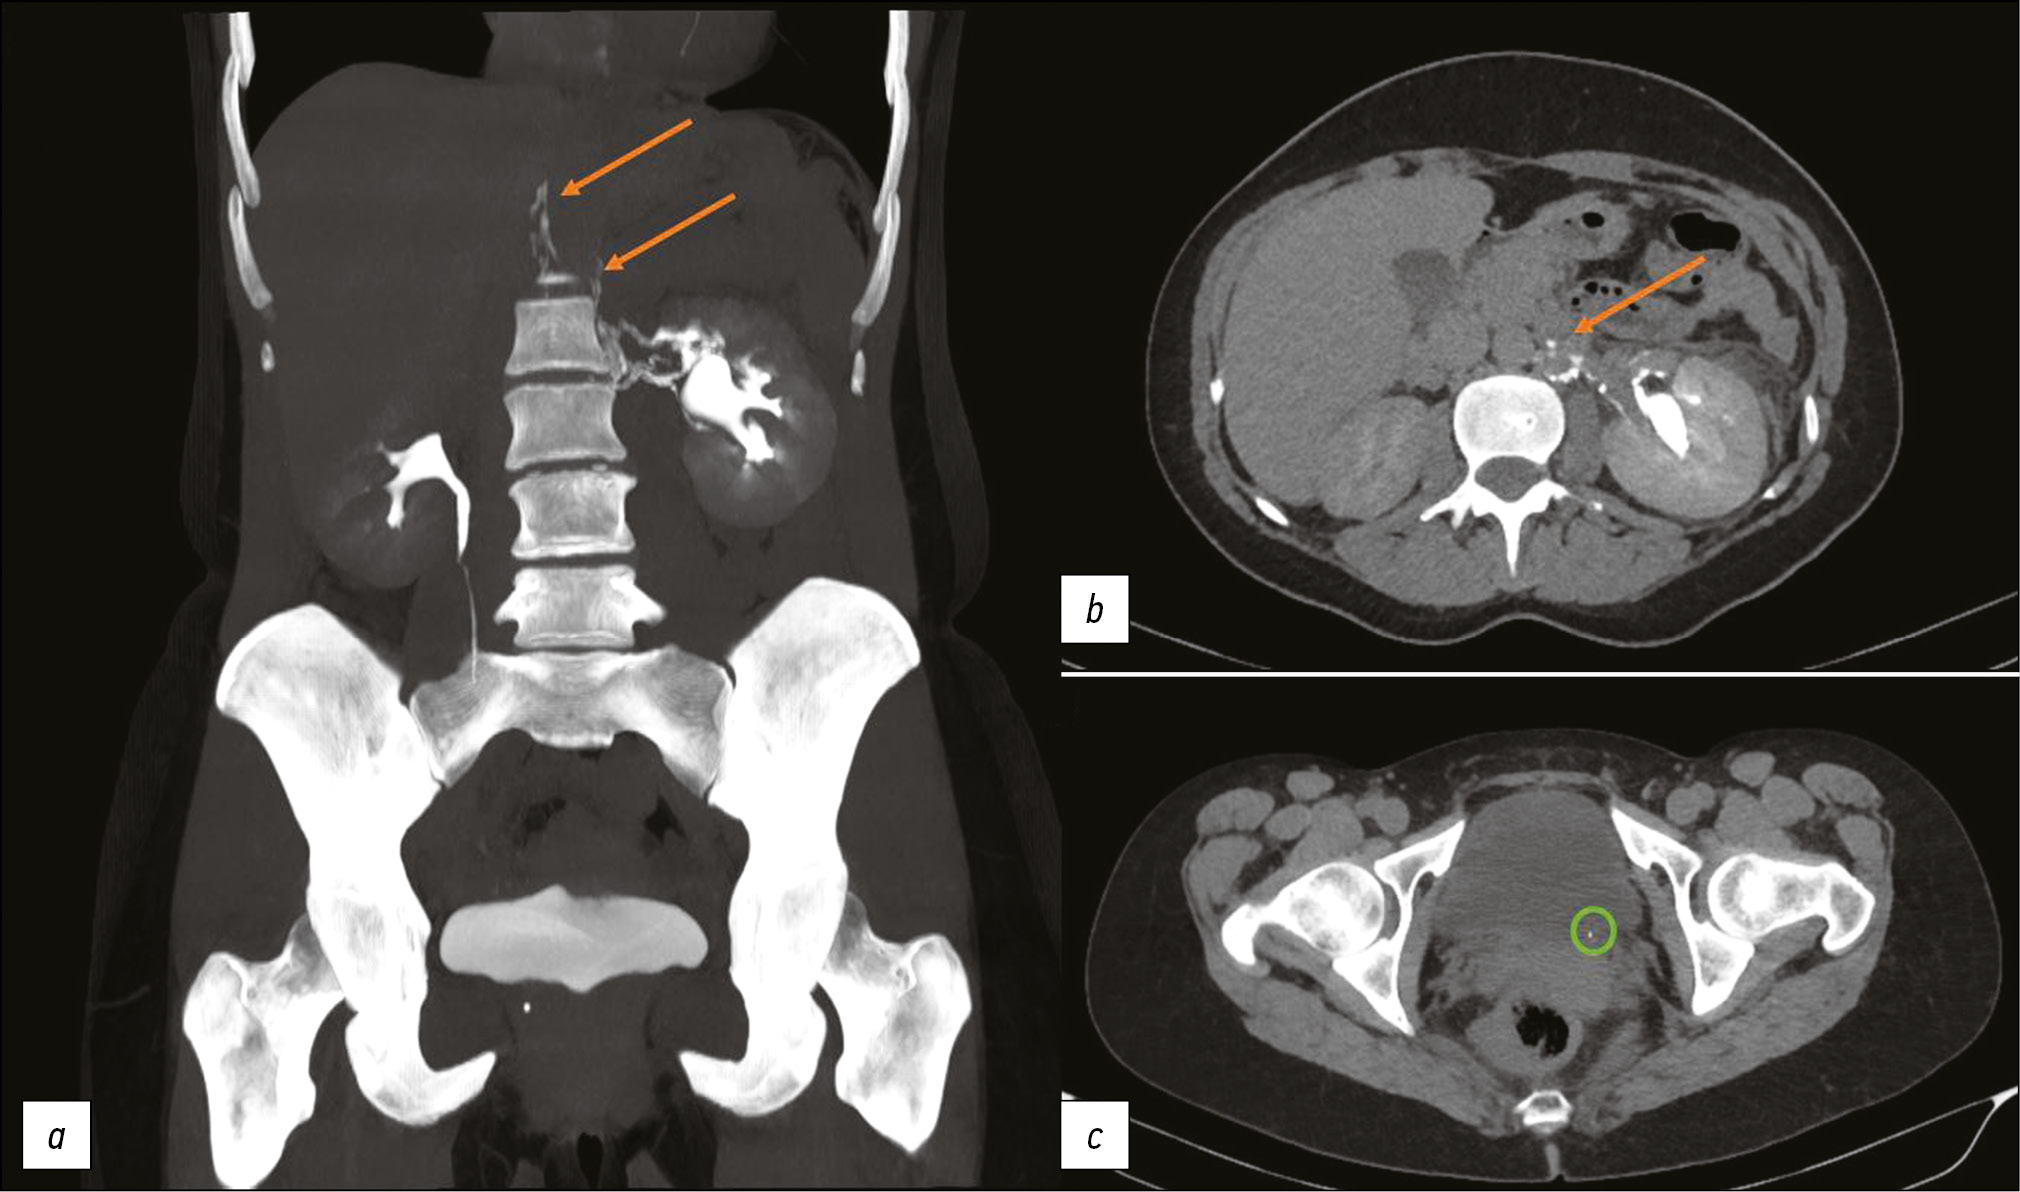

Computer tomography of uro-lymphatic fistulas associated with renal colic

This article presents two clinical observations of uro-lymphatic fistulas diagnosed by computed tomography. In both cases, the patients were admitted with symptoms of renal colic. Uro-lymphatic fistulas are a rare condition caused by the formation of a connection between the urinary and lymphatic systems, which is caused by, as a rule, lymphatic vessel obstruction due to parasitic infestation. Other causes may be radiation therapy, retroperitoneal trauma, and tumor sprouting. In the era before antibiotics, infectious processes such as xanthogranulomatous pyelonephritis and renal tuberculosis were common. Cases of uro-lymphatic fistulas formed against urolithiasis background are presented below. In the clinical cases presented, urine directly entered the lymphatic vessels through a uro-lymphatic fistula detected on contrast-enhanced computed tomography. Uro-lymphatic fistulas caused by impaired urine outflow due to blocked urinary tract are rarely detected since abdominal ultrasound is the diagnostic method of choice in renal colic. In the vast majority of cases, uro-lymphatic fistulas are treated conservatively and do not require surgical intervention. As a rule, the formed fistulas cease to exist when its root cause is successfully treated.